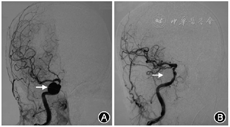

患者女性,82岁。因视物重影5个月,于2017年12月4日至北京协和医院就诊。患者5个月前无明显诱因出现视物重影,伴右侧额面部轻微痛觉,否认视力下降,无恶心、呕吐、耳聋、耳鸣,无语言及吞咽障碍,无肢体感觉及运动障碍,无自主神经功能障碍。既往高血压病史30年,最高血压(高压/低压)202/91 mmHg(1 mmHg=0.133 kPa),平时控制在160/70 mmHg左右;冠心病10余年,现冠心病二级预防治疗中。眼部检查:右眼外转绝对受限。视野示右眼鼻上象限、左眼颞上象限局部视野缺损,伴黄斑回避(图1)。头部核磁共振平扫示右侧海绵窦旁类圆形流空影(图2),提示右侧颈内动脉海绵窦段动脉瘤;右侧海马后部异常信号(图3),建议进一步增强检查;双侧额顶叶、双侧侧脑室旁、基底节区及桥脑多发异常信号,慢性缺血性改变可能。计划入院进一步行头部血管检查。入院后眼部检查:矫正视力右眼为0.5,左眼为0.6;眼压右眼为14 mmHg,左眼为14 mmHg;右眼显性内斜,左眼正位。右眼外转受限,左眼各方向运动无明显受限。双眼睑无水肿、下垂。双眼结膜无明显充血,角膜透明,无角膜后沉着物,前房深度正常,房水清,虹膜纹理清,无前后粘连。双眼瞳孔等大同圆,对光反射灵敏,相对性瞳孔传入障碍(-)。双眼人工晶状体在位。双眼玻璃体轻度混浊。双眼视盘边界清晰,颜色淡红,血管走行大致正常,视网膜在位,未见出血、渗出,双眼黄斑区色素紊乱。入院后为进一步确诊,行头颈CT血管造影容积再现检查,结果显示右侧颈内动脉虹吸段动脉瘤,大小约15 mm×19 mm(图4);头颈部动脉多发粥样硬化改变伴部分血管狭窄;双侧额顶叶、侧脑室旁、基底节区及脑桥多发稍低密度影,缺血改变可能。因而患者主诊断为右侧颈内动脉海绵窦段大动脉瘤,右侧展神经麻痹。患者于2017年12月29日全身麻醉下行数字减影血管造影检查(图5中A),见右侧颈内动脉虹吸段一动脉瘤,大小约20 mm×17 mm,动脉瘤远端颈内动脉床突段局部狭窄,狭窄约80%,左椎动脉起始部狭窄约70%,基底动脉局部狭窄约90%。遂同时行支架辅助动脉瘤栓塞术,术后再次造影示动脉瘤栓塞完全,颈内动脉血流顺畅(图5中B)。术后1周患者右侧面部感觉有好转,但右眼外转受限无明显改善。术后6个月随访,患者临床情况稳定,右眼外转受限仍无明显改善,视野表现大致同前。